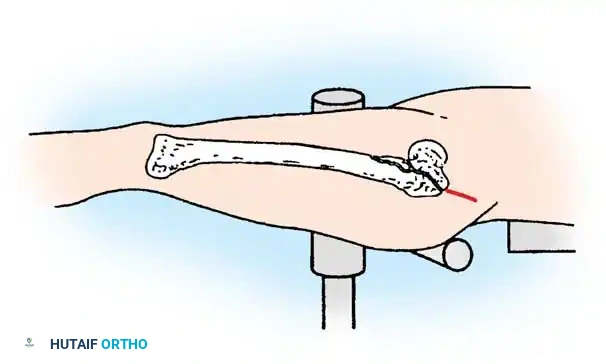

1. Patient Positioning and Reduction

The patient is placed supine on a radiolucent fracture table. The operative leg is secured in a traction boot, and the well leg is placed in a hemilithotomy position or scissored posteriorly to allow unobstructed access for the C-arm fluoroscope.

Proper patient positioning on the fracture table is paramount. Ensure the C-arm can freely rotate from AP to lateral without obstruction.

Closed Reduction Maneuver:

1. Apply longitudinal traction to restore leg length.

2. Internally rotate the leg (typically 10 to 15 degrees) to correct the external rotation deformity and bring the femoral neck parallel to the floor.

3. Verify reduction on both AP and lateral fluoroscopic views. An acceptable reduction must have cortical apposition medially and anteriorly.